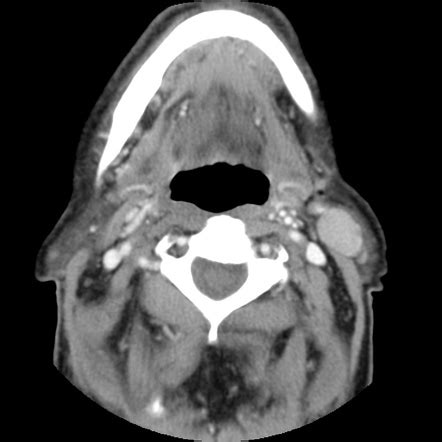

CT scan findings:

• The right parotid gland is bulky compared to contralateral site.

• An ill-defined hyperdense (HU 36- 42) lesion with smooth margin (yellow arrows) is seen at the inferior portion of right parotid gland, measures about 2.0 cm x 2.1 cm x 2.9 cm (AP x W x CC).

• In post contrast images, the lesion is homogenously enhanced almost similar to the rest of the parotid tissue.

• No calcification within the lesion.